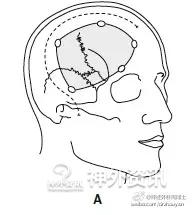

图示额颞开颅-额下入路的发展历程。注意观察皮肤切口和骨瓣大小的变化。A. Dandy的额颞入路;B. Yasargil的翼点入路(应用显微外科技术);C. 眶上keyhole开颅入路:显露Yasargil翼点入路的额底部分,显著缩小了开颅范围,也显著降低了颅内、外的手术创伤。

1971年,Donald H. Wilson提到:“我们不迷信,也不盲目崇拜keyhole手术。巨大的动静脉畸形、大脑半球切除以及癫痫外科都必须要使用标准的大范围开颅手术。”各位一定要清楚,说这句话的Wilson是首先使用keyhole手术的神经外科医生。

这里,需要强调的是keyhole的概念(这个很重要)——keyhole不仅仅是指开颅的范围大小,而应当是在精准定位的基础上确定合适的手术路径。所以,神经外科keyhole的目的不单纯是开颅的范围大小,更为重要的是最大限度的限制脑暴露的范围和最小程度的牵拉脑组织。故此,小骨窗开颅不是keyhole的目的,而是神经外科微侵袭理念的结果。

A. 标准的大范围开颅,暴露术野深部病变的视角呈漏斗型; B. 这种传统的大范围开颅方法可以被视为若干keyhole手术入路的整合;C. 只要选择正确的小骨窗路径,手术视角呈扇形扩大。路径越短,手术视角越窄;而路径越长(术野深部病变),手术视角则越宽。这种路径选择方法,有时还可同时处理对侧的病变。